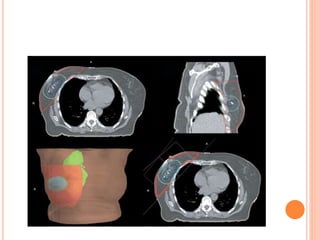

3D CRT AND RTOG GUIDELINES

PLANNING CT

 Take planning CT from

hyoid to cover marked

lower border

 3mm cut will be ideal

DURING CT SIMULATION

Post-BCS

Post-Mastectomy

REGIONAL NODAL CONTOURING